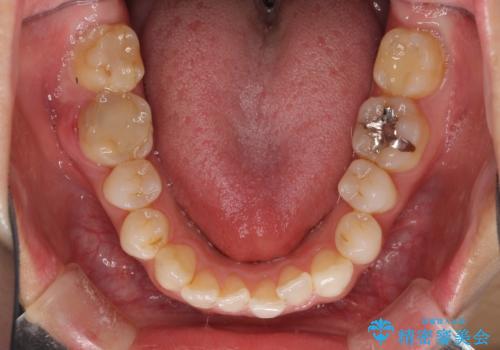

- 審美的ではない上の前歯とデコボコの下の前歯、歯茎が腫れている奥歯を気にして来院された患者様です。

根管治療の必要な歯がいくつかあるため、まずは根管治療を行い、その後インビザラインにて矯正治療を行うこととしました。